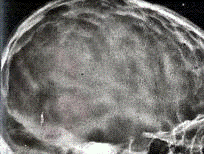

Рентгенографія черепа: зростання

розмірів черепу, розходження швів, посилення "пальцьових вдавлень",

поглиблення ямок основи черепу, витончення кісток черепу. Ь)